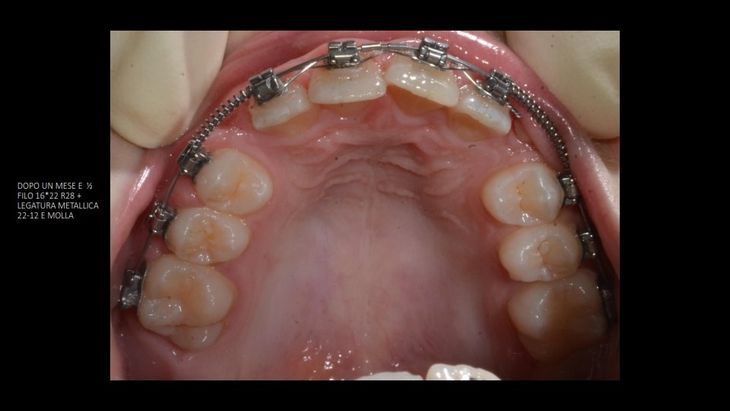

Alcuni casi dello Studio